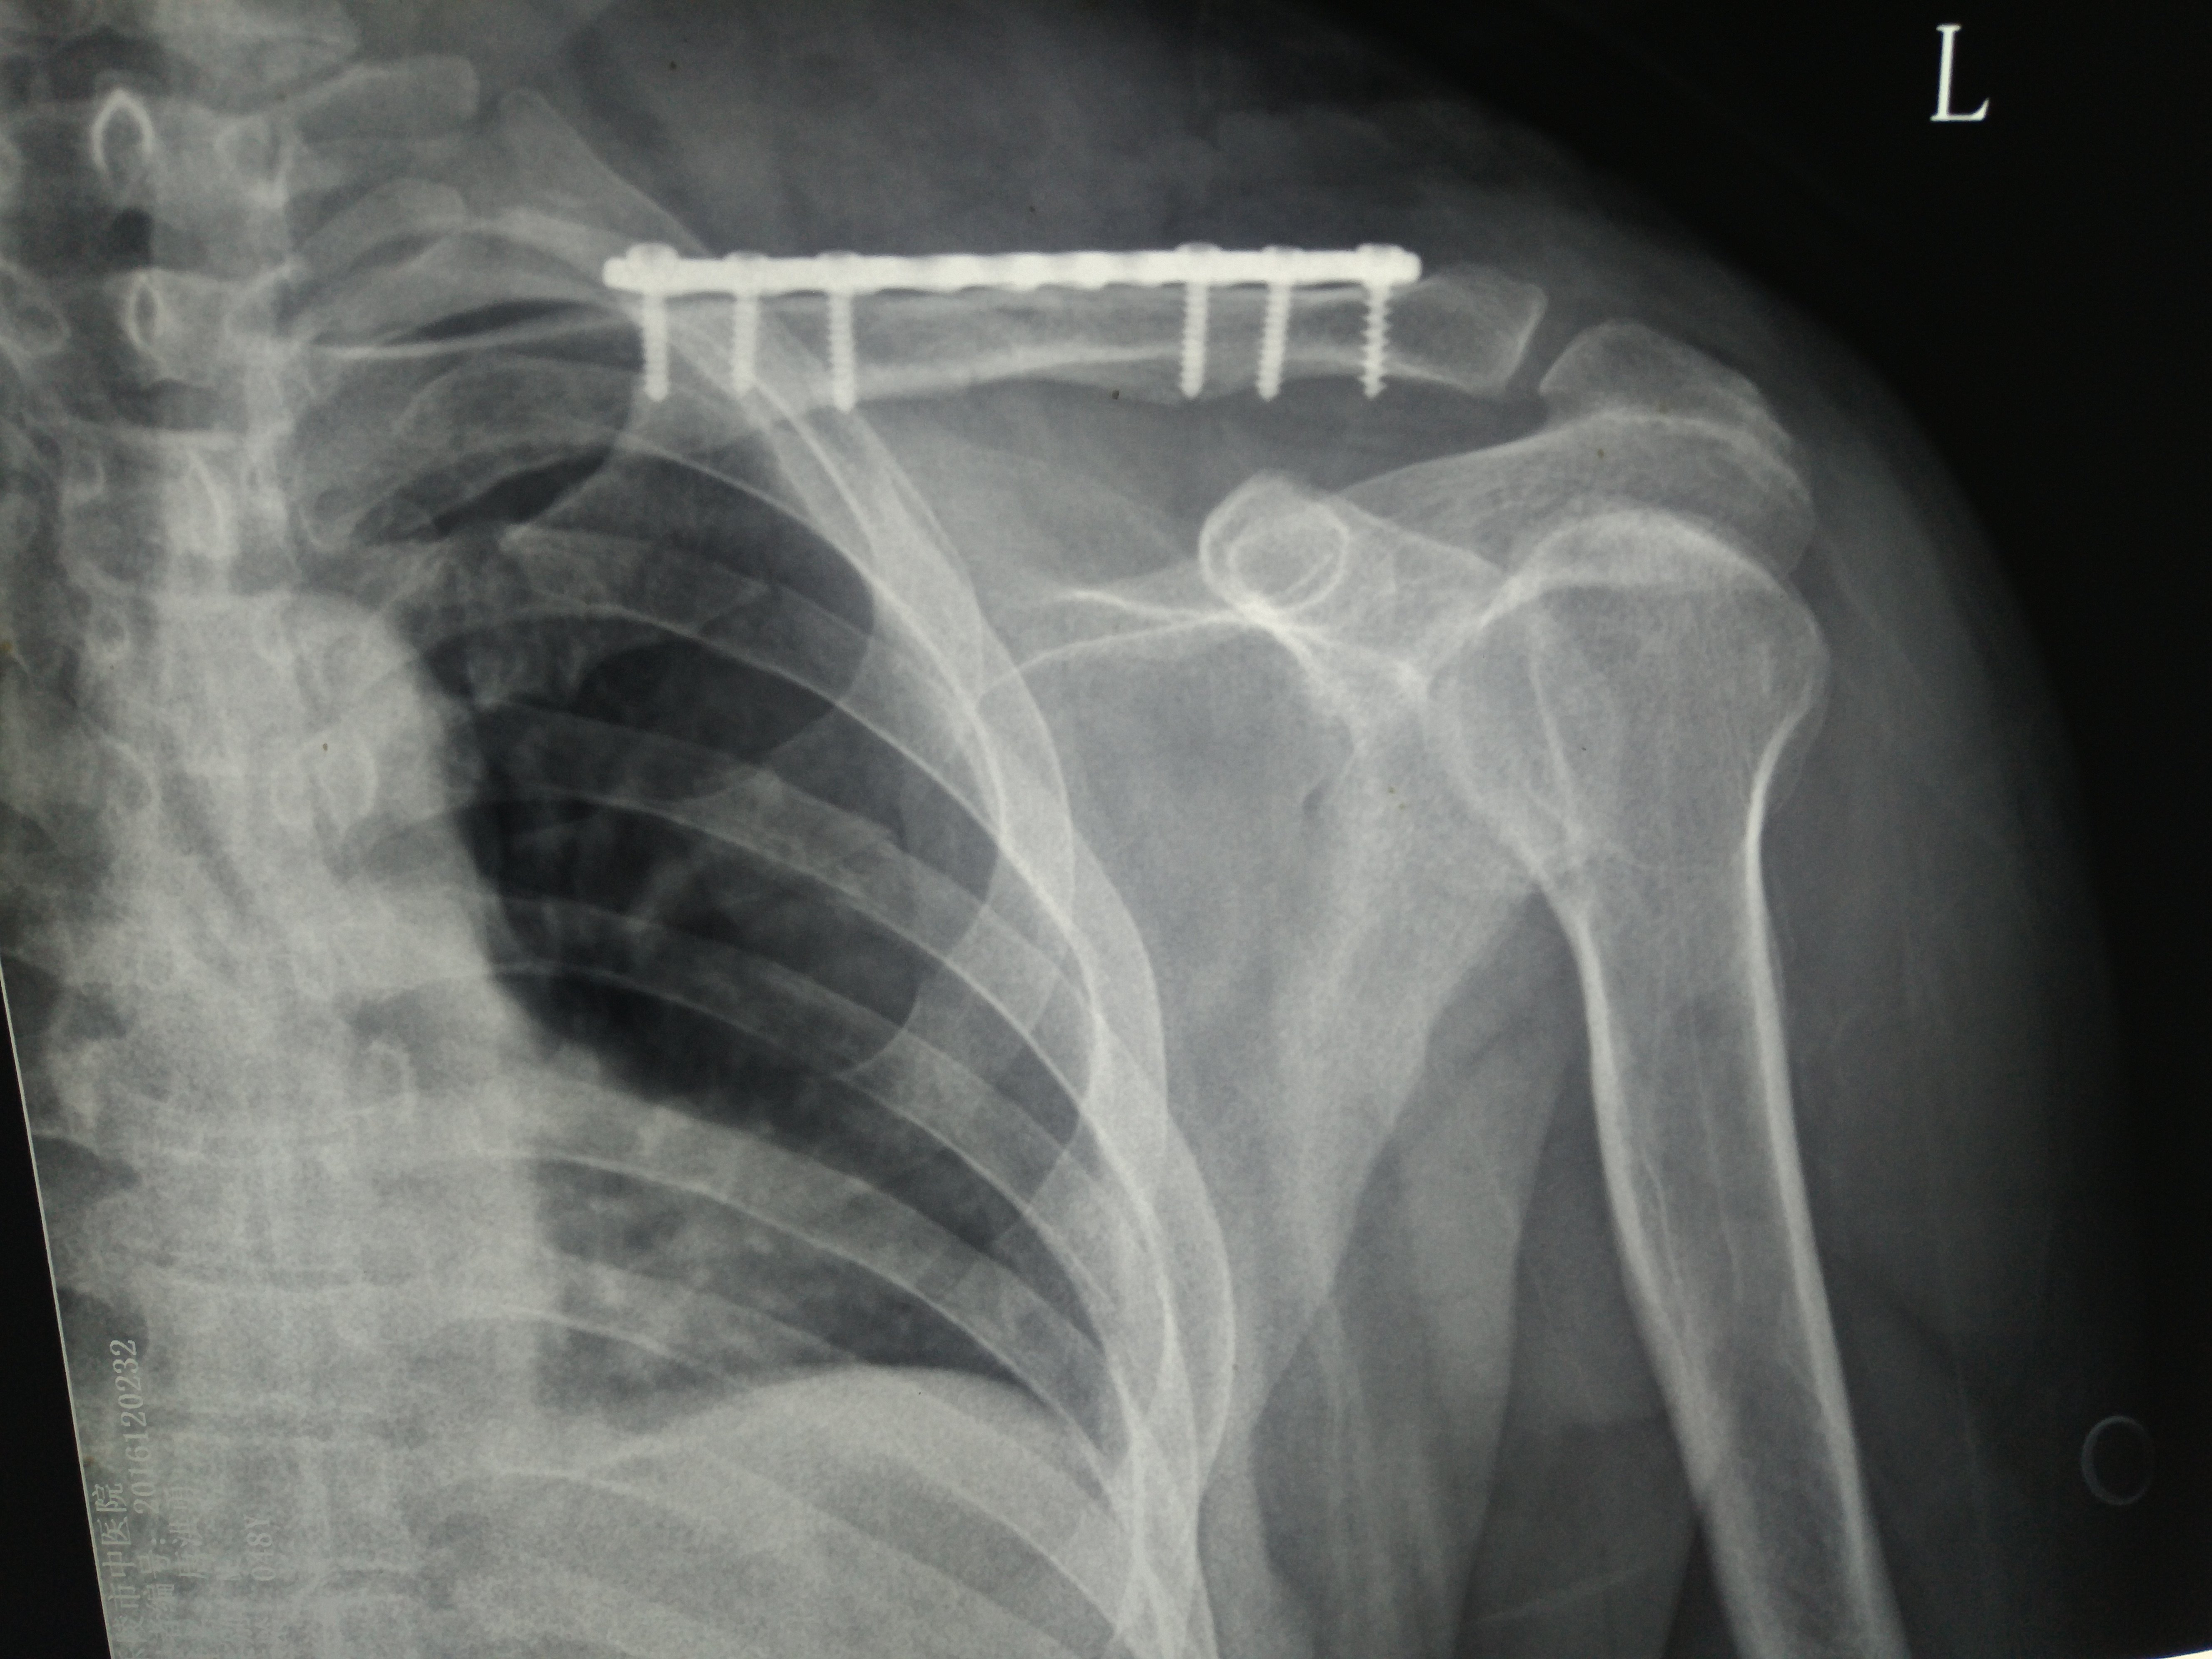

骨折部の ズレが大きかったり 、 骨が外に飛び出す ような 開放骨折 や鎖骨の下にある 神経や血管 が傷ついているような場合は 手術 が行われます。 手術には、 鎖骨の中に鋼線を入れて固定 する方法( 髄内釘固定 )や金属の板を鎖骨にあてて 螺子で固定 する方法( プレート固定 )などが鎖骨が骨折した場合は、患者に石膏固定を施すか、またはきつい包帯を貼る。 治療法の選択は骨折の複雑さに依存するため、適切に分類することが重要です。 鎖骨骨折治療法の基本は骨片の完全性を回復することです。 鎖骨が骨折した場合は、患者に石膏固定を施すか、またはきつい包帯を貼る。 治療法の選択は骨折の複雑さに依存するため、適切に分類するあと鎖骨骨折では あわせて、手がしびれたりなどの 神経障害を疑う場合、 そんな重症の骨折を疑う場合は、 時間を問わず 整形外科医がいる 救急外来に連絡して受診しましょう。 そうでなければ、 rice療法を徹底して、 翌日の朝イチで、整形外科受診でも大丈夫です。 外来でやることは診察→レントゲン→整復固定→レントゲン

鎖骨骨折では、手術をしない場合とする場合があります。 手術しない場合 鎖骨は比較的癒合しやすい骨ですので、ずれが小さい場合には手術は行われません。 鎖骨バンドや三角巾などで骨折部を固定して、骨の癒合を待ちます。左鎖骨骨幹部 骨折と診断され, 術前X線所見からはNordqvistPeterson分 類Group1Cで中間骨片の転位が認められた(図2a) その他 骨折や肩関節疾患は認められなかった受傷翌日 , 左鎖骨骨 幹部骨折に対してロッキングプレートによる骨接合術が施行 された(図2b)鎖骨骨折の治療ってどんなことをするの? 鎖骨中央1/3の骨折 一番多い中央1/3の骨折では、通常は、 保存療法 を行います。

ただし、骨折のズレ方や骨の折れ方(粉砕型など)も様々ですから、ワイヤーで骨折部を巻いたり、大きめの板状の金属(プレート)を鎖骨の上に設置して固定したりすることもあります。 鎖骨骨折は基本的には骨のくっつき(骨癒合:こつゆごう)が良好な骨なので、多少のズレは許容される のですが、 鎖骨遠位端は骨が平らな形状になっていき、骨のくっつきも右鎖骨遠位端骨折に対しWplate固定術施 行。整復位、骨癒合ともに良好である。本症 例のJOAscoreは92点、外転可動域は術後8 週で140度、抜釘後170度と良好な結果であ 肩鎖関節脱臼および鎖骨遠位端骨折に対するフック付プレート固定術後の可動域について 19鎖骨骨幹部骨折治療の基本は保存治療である。 しかしRobinsonらは保存治療とプレート固定では、偽関節率は保存治療で有意に 高かったと報告し 5) 、Murrayらは危険因子として転位の大きさ、粉砕、喫煙を挙げている(図3) 6) 。